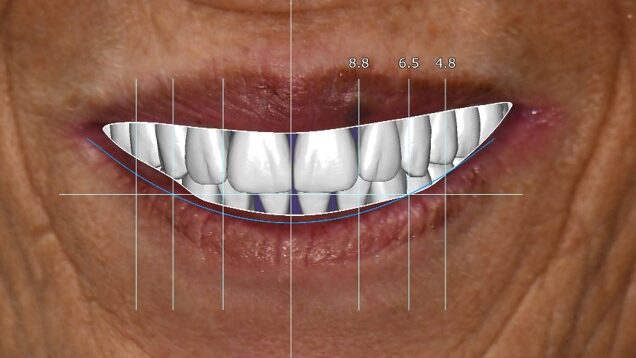

A 55-year-old woman presented with a chief complaint of wanting to complete the treatment of her maxilla and mandible that had begun elsewhere a number of years ago. The patient reported that she had several implants placed and provisional bridges inserted a number of years ago. A review of her medical history revealed no significant findings. A clinical exam was performed, and the following data was collected: a full mouth series radiographic survey, a cone beam CT scan, intraoral surfaces scans, full face and intraoral photos (Figs. 1,2,3).

Fig. 1

Fig. 2

Fig. 3

The data recorded during the clinical exam in conjunction with the FMS xrays and CT scan data were analyzed, and a diagnosis was made as to the viability of the patient’s existing teeth. A virtual diagnostic wax up was completed using prosthetic planning software (ExoCad) (Figs. 4A, 4B). The .STL file of the virtual wax up was integrated with the CT scan data in implant surgical planning software (3Shape Implant Studio) and a surgical plan was designed (Figs. 5A, 5B). The viability of this surgical plan was then evaluated in conjunction with the previously determined prognosis of the patient’s existing dentition and surrounding periodontium, and a treatment plan was formulated. The plan with the anticipated predictability of achieving the planned result was presented to the patient. The patient approved the treatment plan.